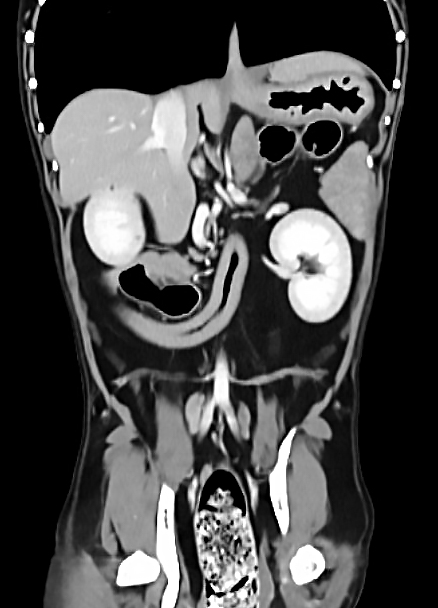

| 복부 | 간, 비장, 신장, 위장관 종양 및 결석, 부신, 림프절 등 |

복부 장기의 종양, 염증, 결석, 기형 등 고해상도 분석